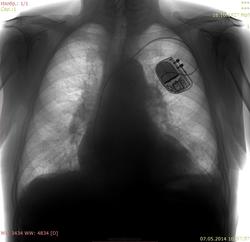

Пациент 1927 г.р, проф флг, архива нет, несколько лет назад перенес левостороннюю пневмонию. Похоже ли на саркоидоз (расширение корней, усиление рисунка, слева подчеркнута тень соска)?

А мне почему то кажется, что дела сердечные здесь.

Прежде всего , учитывая тень экс ( ивр) нужно исключать сердечную недостаточность.

Похоже на р-признаки застоя в малом круге кровобращения: расширение сердечной тени, расширение корней за счет сосудов, симптом "скачка калибра".

Сердечные дела.

Возможно, требуется подзарядка или замена ИВР. Если есть возможность - быстренько глянуть пульсацию на скопии.

А есть ли здесь признаки застоя?

Застой по мкк. Хотя левый желудочек почти не расширен, но корни расширены.